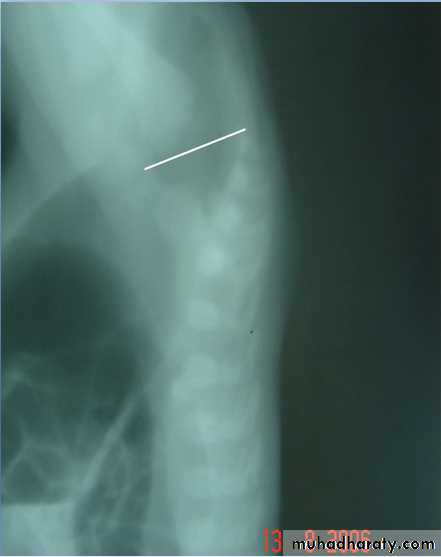

Radiology

Determined:1-relation of rectum to sphincter muscle.

2-associated anomalies.

1-x-ray of the spine and chest (sacral , VATER).

2-Lateral invertogram ( pubococcegeal line) 18-24hr.after birth.

-gas shadow above this line suggest high type.

- gas shadow below suggest low type.

3-lateral decubitus X-ray.

4-M.R.I.